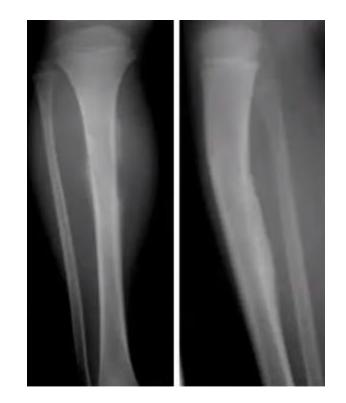

Twisting Injury Cases

Q1: What is the mechanism of this injury?

- Spiral fracture caused by indirect twisting injury

Q2: What is the treatment of choice?

- Surgical treatment is best

- Conservative options if minimally displaced: Long leg cast for 4-6 weeks, Patella-bearing cast (Sarmiento) or fracture brace

- Average union time is 16ยฑ4 weeks

- Operative treatment: Intramedullary (IM) Nailing is the treatment of choice

Tibial Fractures

Tibia and Fibula Fracture

Diagnosis: Segmental and comminuted fracture of tibia and fibula